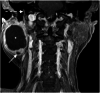

Figure 2. T1 VIBE fat-saturated image.

In a post-gadolinium image, the peripheral solid component enhances, surrounding the central non-enhancing hypointense cystic component (*). A smaller cyst (arrow) is also noted within the peripheral solid component. Note the normal mastoid segment of the right facial canal (dotted arrow) in relation to the parotid lesion.